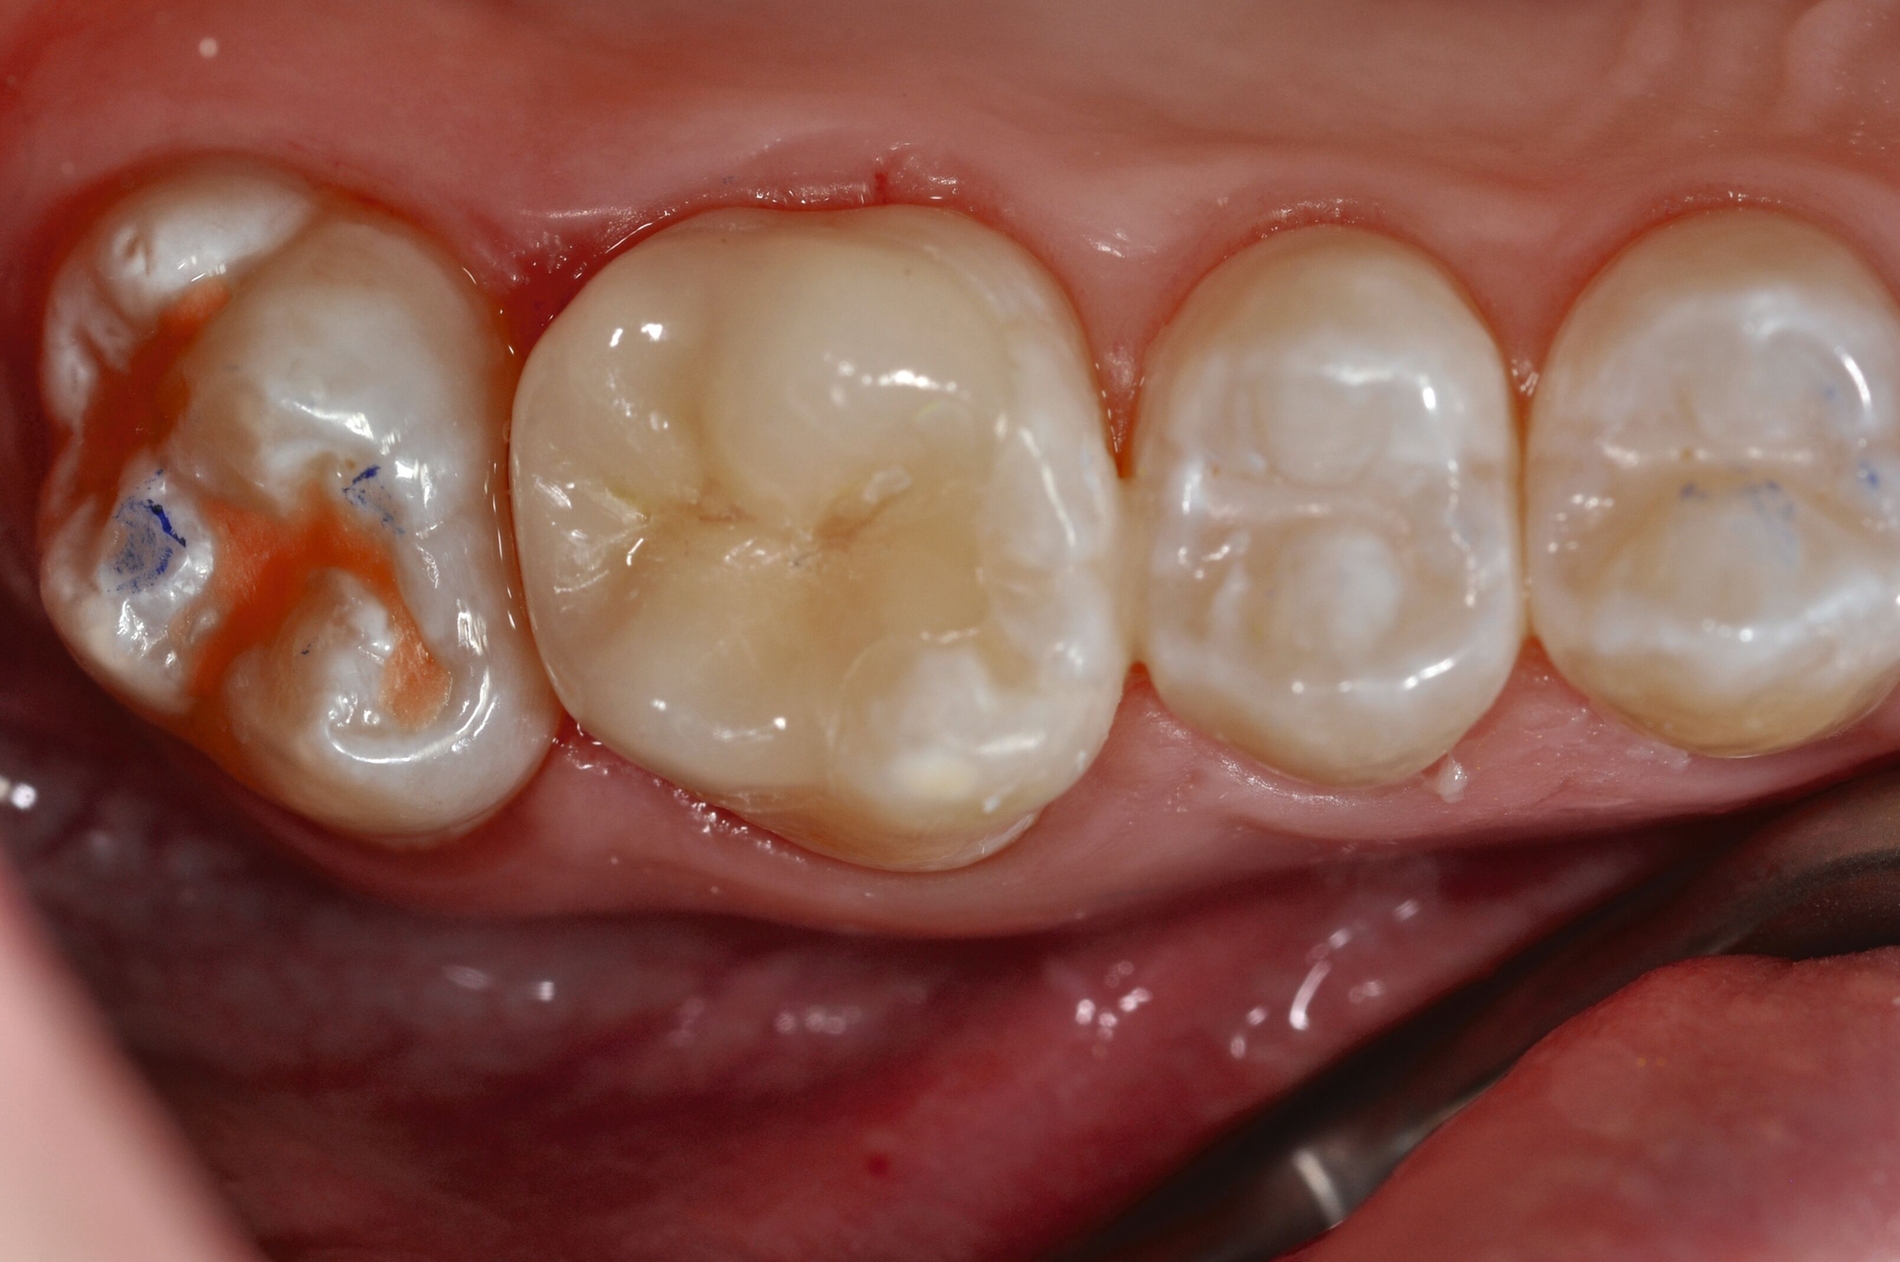

Diese Klassifikation dient als Grundlage für die Therapieempfehlungen. Deutlich wird, dass aufgrund der Symptomatik die Therapie der Zähne höchst unterschiedlich ausfällt. Dass etwa eine Opazität ohne Überempfindlichkeit (Index 1, Abbildung 1) ein anderes therapeutisches Vorgehen erfordert als ein Zahn mit nahezu komplettem Einbruch der Zahnoberfläche und mit Hypersensitivität (Index 4, Abbildung 2), ist offensichtlich.

Für die zahnärztliche Praxis gibt die Einteilung eine Orientierung darüber, welche Behandlungsmaßnahmen erforderlich sind beziehungsweise eingesetzt werden können. Je nach Schweregrad wird dabei zwischen nichtinvasiven und invasiven Maßnahmen sowie einer kurzzeitigen oder längerfristigen, restaurativen Therapie unterschieden. Bei der Überarbeitung des Konzepts wurde zudem zwischen Front- und Seitenzähnen differenziert (Abbildung 3) [Bekes et al., 2023; Steffen et al., 2017].